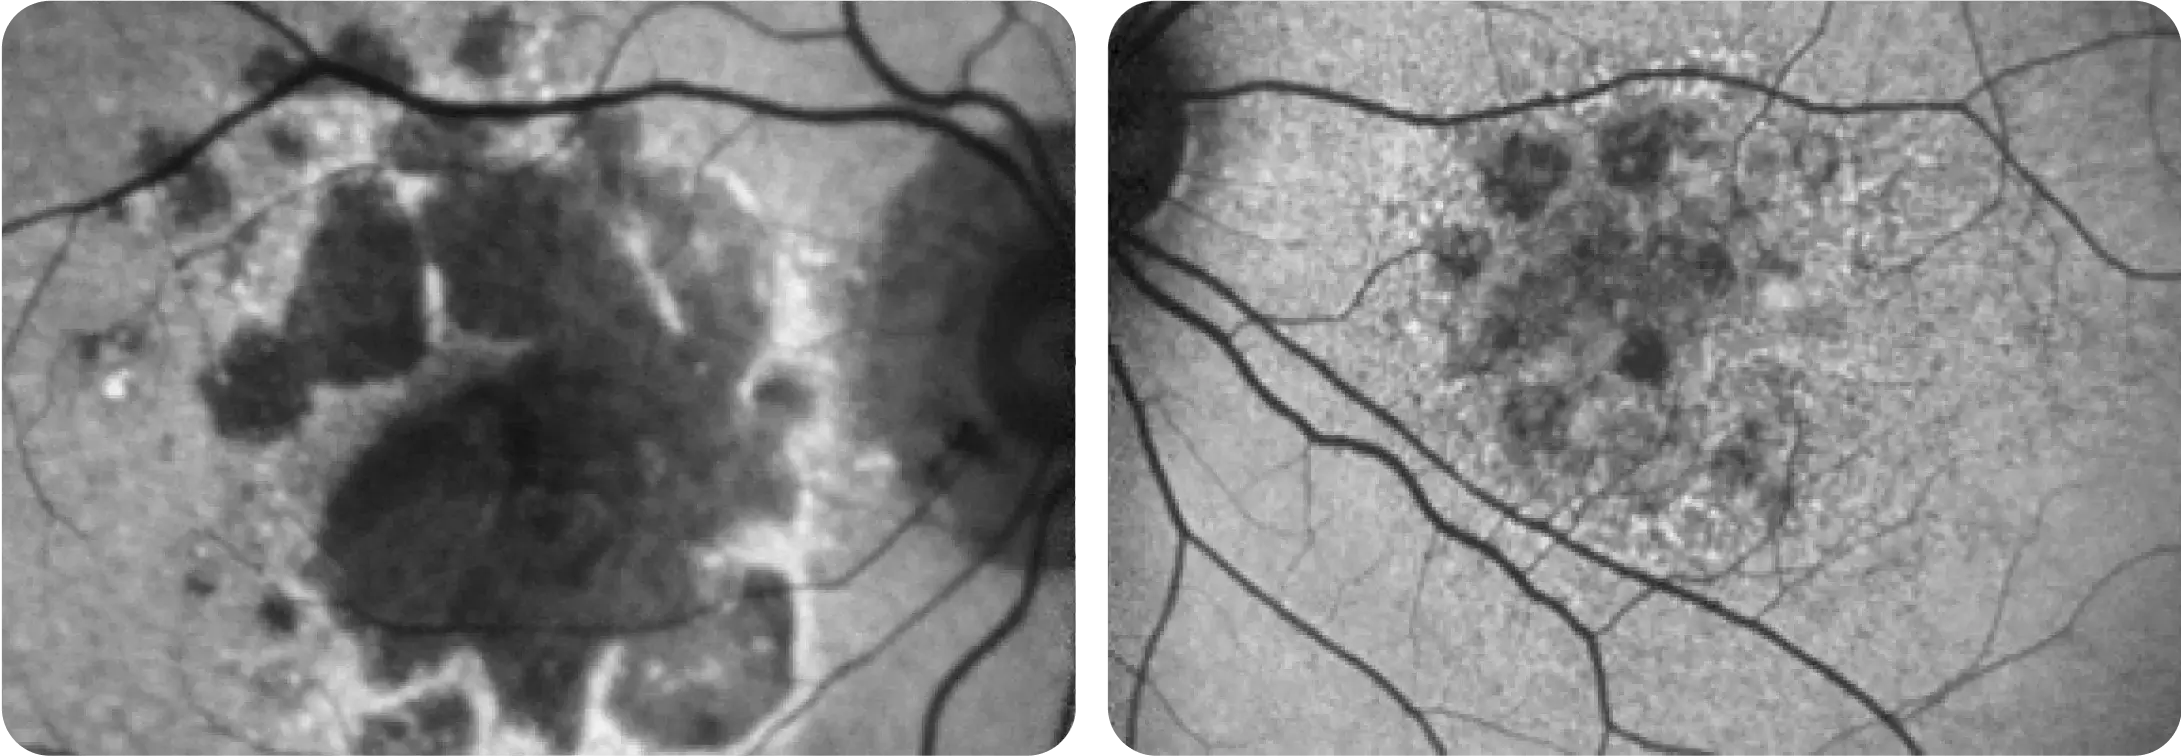

Neovascular AMD

- In clinical trials, use of IZERVAY was associated with increased rates of neovascular (wet) AMD or choroidal neovascularization (7% when administered monthly and 4% in the sham group) by Month 12. Over 24 months, the rate of neovascular (wet) AMD or choroidal neovascularization in the GATHER2 trial was 12% in the IZERVAY group and 9% in the sham group. Patients receiving IZERVAY should be monitored for signs of neovascular AMD.

IZERVAY™ (avacincaptad pegol intravitreal solution) is indicated for the treatment of geographic atrophy (GA) secondary to age-related macular degeneration (AMD)